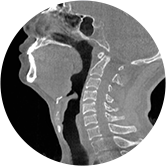

• 頸椎

• 腰椎